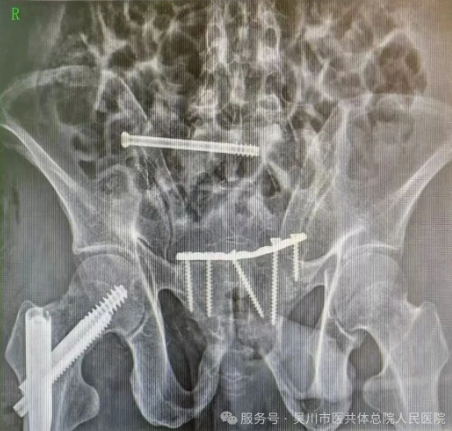

骨外科一区主任、主任医师李德强,立即带领专家团队对患者的各项身体指标、受伤情况等进行综合评估,缓解家属的焦虑情绪。最终决定为患者施行损伤控制手术,稳定患者的生命体征,待其血流动力学稳定后,再二期采用微创小切口的方式来修复骨盆以及股骨多段骨折。